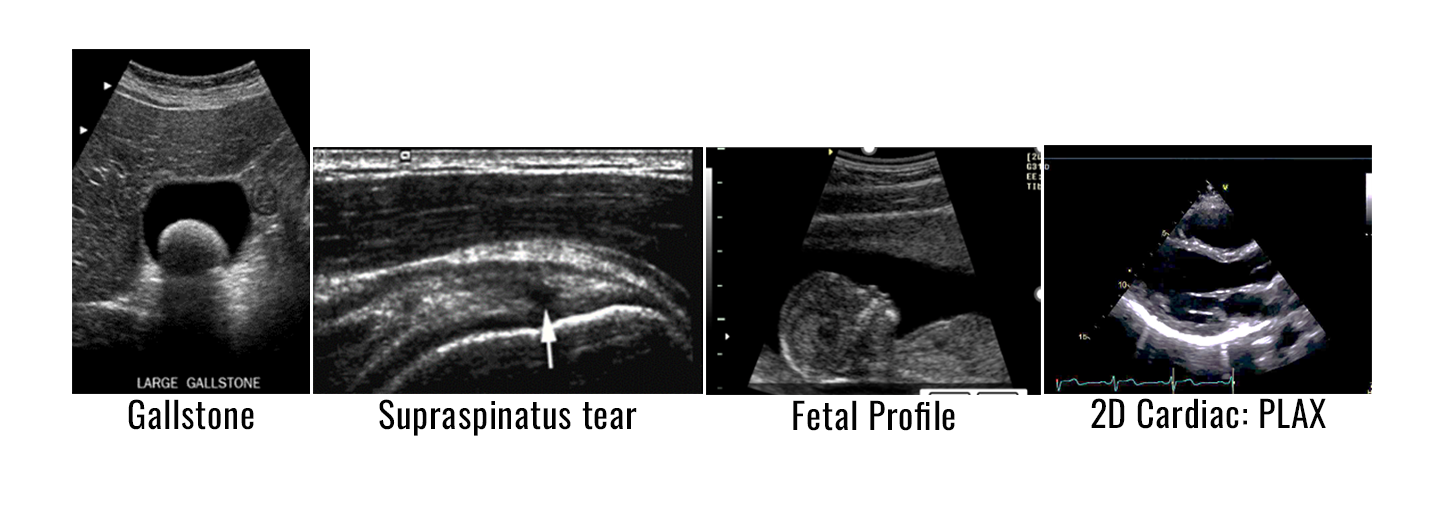

POCUS is a quick, focused ultrasound exam performed and interpreted at the bedside by the medical provider. POCUS can be effectively utilized for a variety of applications ranging from abdominal, OB-GYN, cardiac, soft-tissue/MSK, trauma, pulmonary, and procedural guidance.

POCUS can be used from “head-to-toe” to evaluate a range of medical conditions but can be streamlined depending on the providers’ scope of practice and type of medical facility offering these patient services.